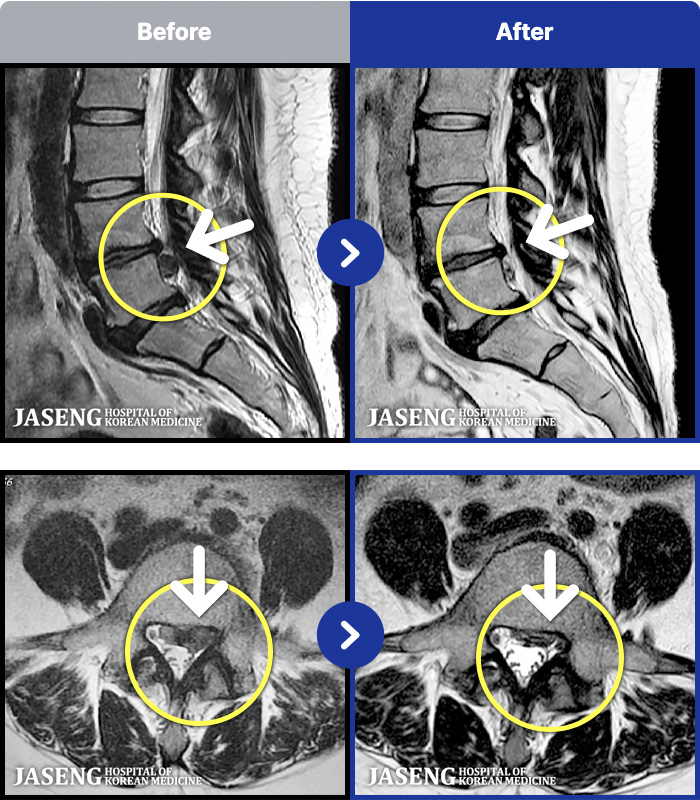

MRI ũ ʸ Ȯϼ.

[뱸] 19.11.28~25.05.06